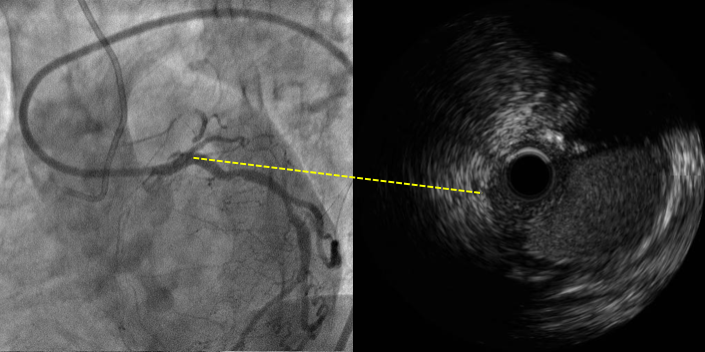

Case : CTO of Ostial LAD

Baseline CAG

MC+ pilot 150/G2, Failed

IVUS in diagonal or in OM?

IVUS in Side branch

LCX coming in

Ostial LAD

结合IVUS图像确认穿刺点及穿刺方向